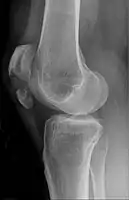

The patella can break in various ways depending on the way it is injured, and into two or more pieces.[1] Types include transverse, the most common, with one fracture line;[5] marginal; osteochondral; and the rare vertical type, or stellate, where a direct compression force gives rise to a comminuted pattern.[5][7] Patella fractures can be further classified as displaced, where the broken ends of bone do not line up correctly and separate by more than 2mm, or undisplaced and stable where pieces of bone remain in contact with each other.[1][7] If fragments of patella bone stick out from the skin it is known as an open patella fracture, and closed if the overlying skin is intact.[1]

Vertical patella fracture